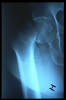

Fractura cuello fémur. Prótesis completa.